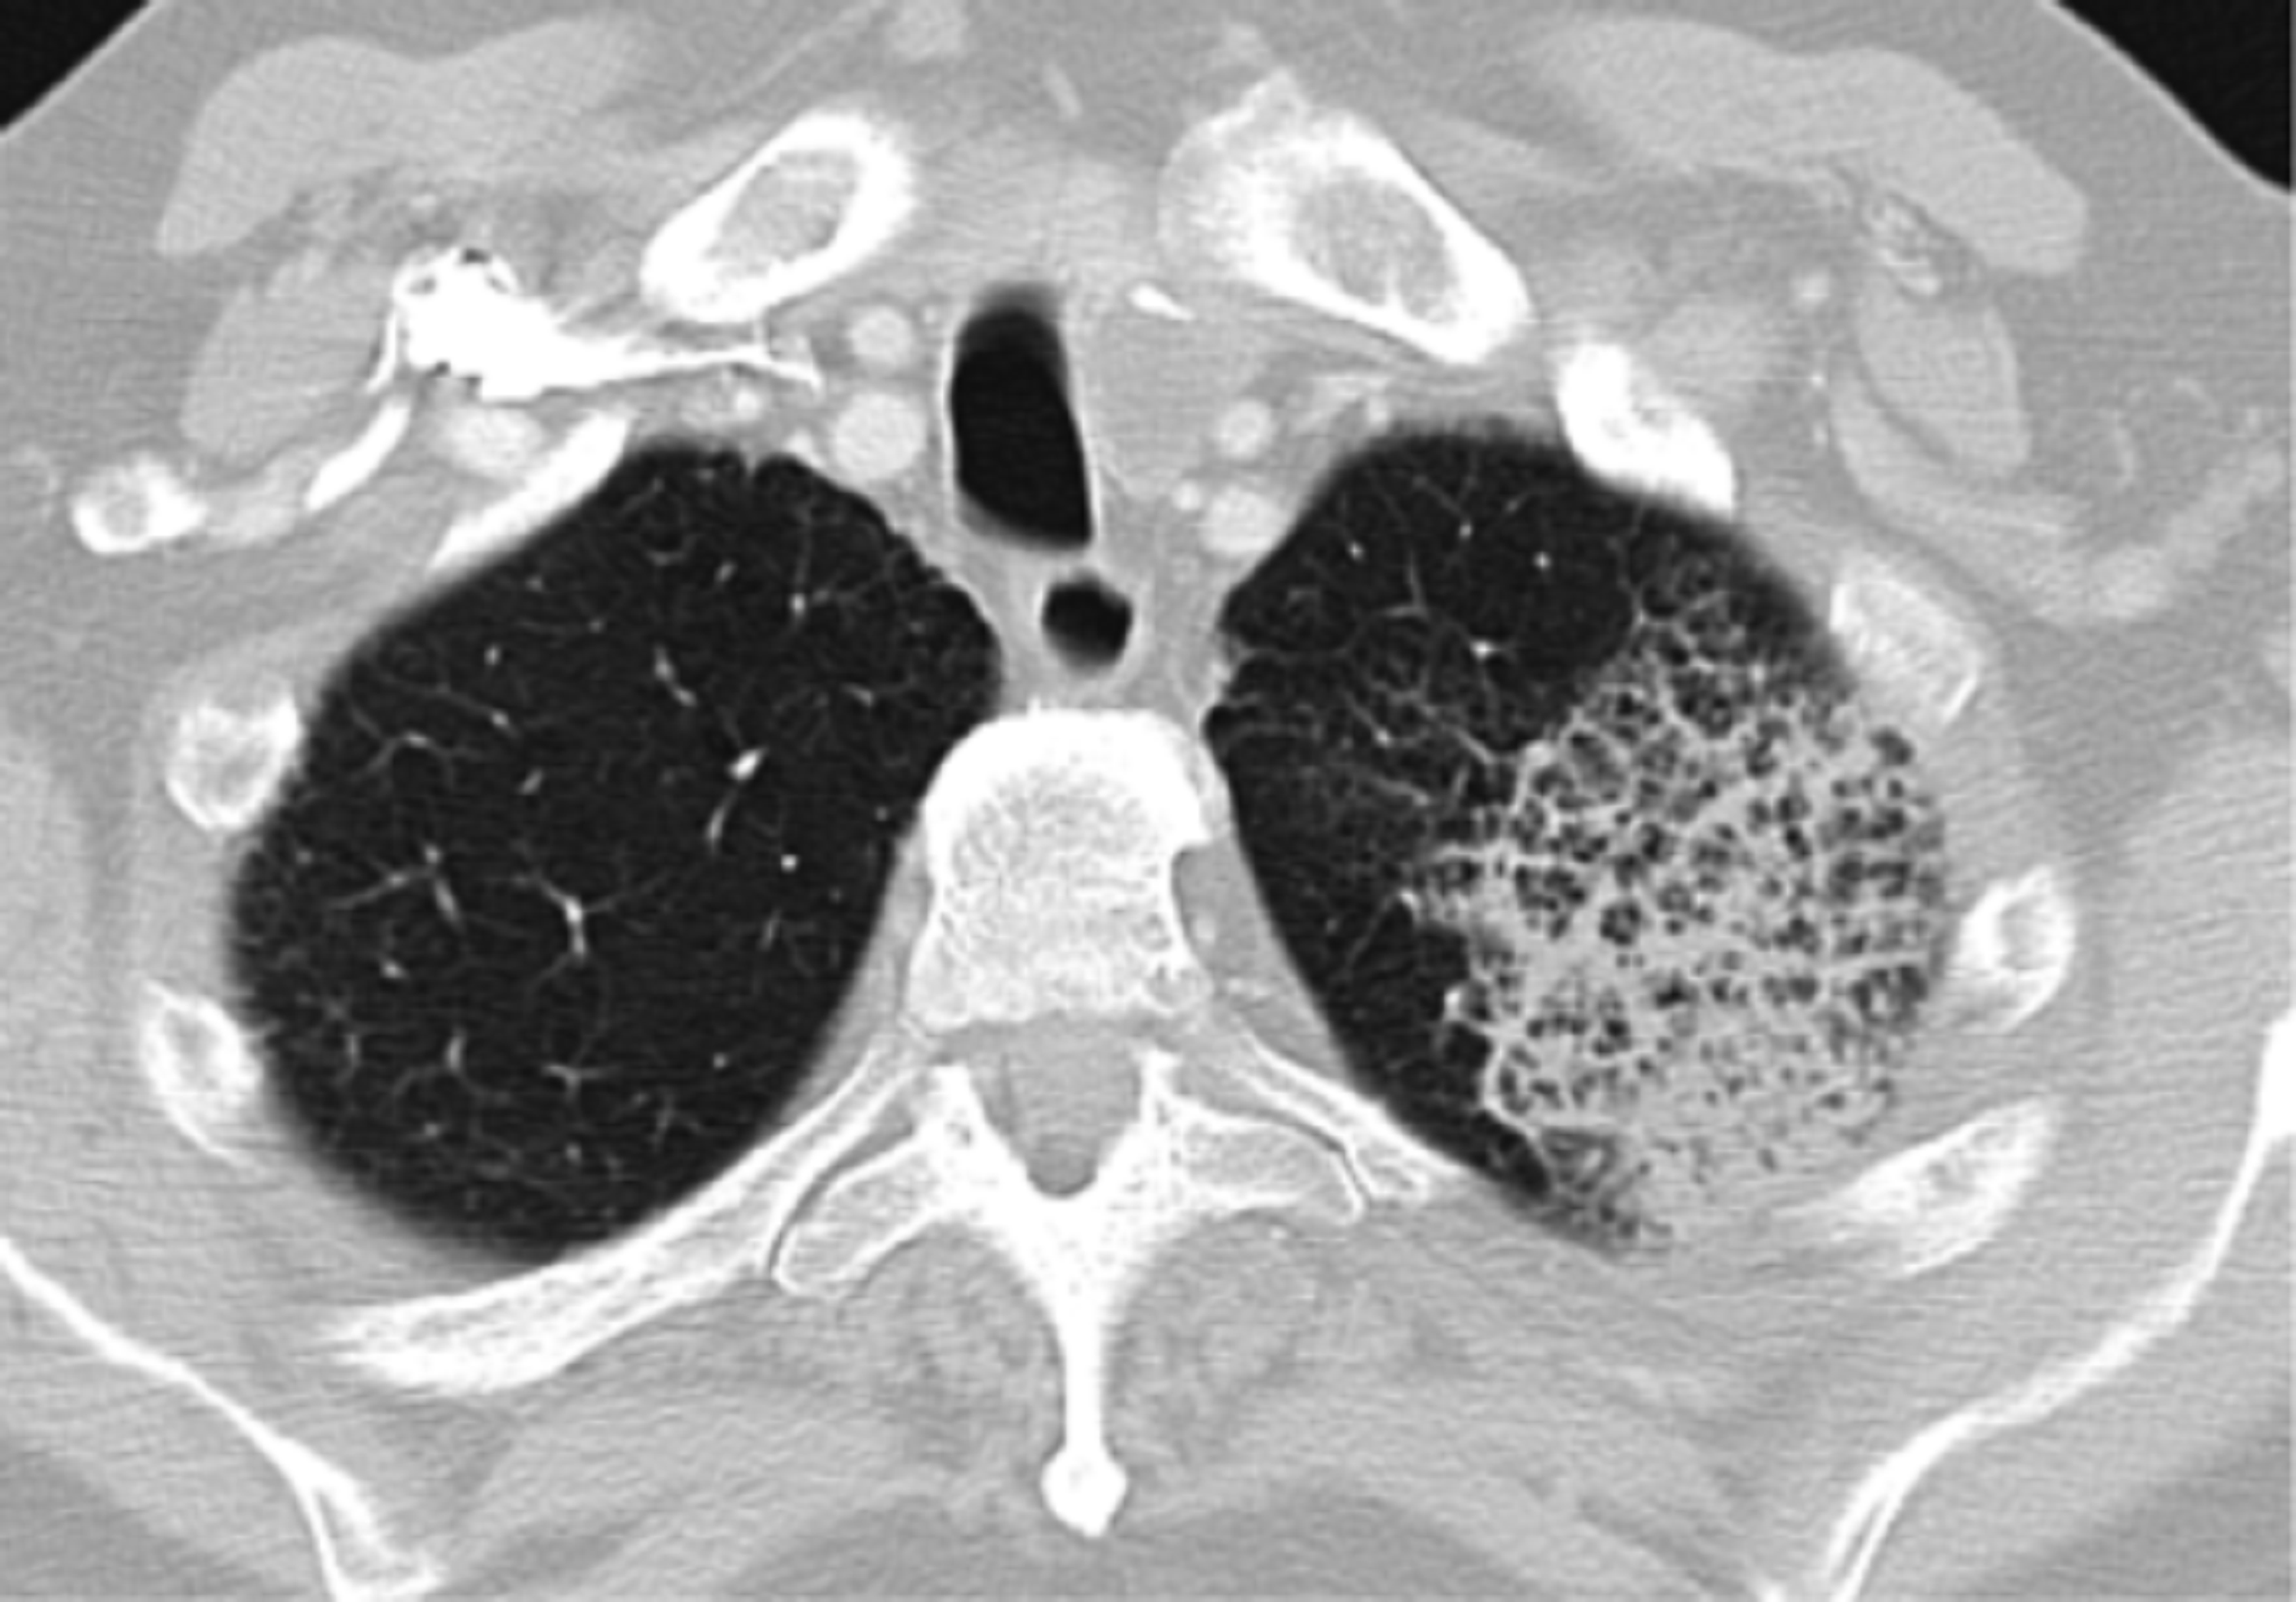

first rule out infection. d/d acquired pneumonia 2) lupus Lupus And Pneumonia Systemic lupus erythematosus (sle) is a chronic systemic autoimmune disease characterized by a wide spectrum of clinical. Systemic lupus erythematosus (sle) is a chronic, autoimmune disorder that can present with a wide array of clinical and immunological abnormalities (1). Background and objective pneumonia remains the main cause of mortality in patients with systemic lupus erythematosus (sle). Learn about the connection. Lupus And Pneumonia.

Forms of systemic lupus erythematosusrelated interstitial pneumonia Lupus And Pneumonia Learn about the connection between lupus and lung disorders, such as pleuritis, pneumonitis, pulmonary emboli, and pulmonary hypertension. Systemic lupus erythematosus (sle) is a complex autoimmune disease with potential multiorgan involvement, including pulmonary involvement,. Differential diagnosis requires exclusion of. Systemic lupus erythematosus (sle) is a chronic systemic autoimmune disease characterized by a wide spectrum of clinical. Although many bacterial infections. Lupus And Pneumonia.

Figure 1 from Bronchiolitis obliterans organizing pneumonia as the Lupus And Pneumonia Systemic lupus erythematosus (sle) is a chronic systemic autoimmune disease characterized by a wide spectrum of clinical. Background and objective pneumonia remains the main cause of mortality in patients with systemic lupus erythematosus (sle). Learn about the connection between lupus and lung disorders, such as pleuritis, pneumonitis, pulmonary emboli, and pulmonary hypertension. Pulmonary manifestations of the disease include disorders of. Lupus And Pneumonia.

Acute lupus pneumonitis as the initial presentation of systemic lupus Lupus And Pneumonia Systemic lupus erythematosus (sle) is a complex autoimmune disease with potential multiorgan involvement, including pulmonary involvement,. Differential diagnosis requires exclusion of. Pulmonary manifestations of the disease include disorders of the lung parenchyma, pleura, and pulmonary vasculature. Systemic lupus erythematosus (sle) is a chronic systemic autoimmune disease characterized by a wide spectrum of clinical. Although many bacterial infections are more prevalent. Lupus And Pneumonia.

Acute lupus pneumonitis as the initial presentation of systemic lupus Lupus And Pneumonia Differential diagnosis requires exclusion of. Systemic lupus erythematosus (sle) is a chronic systemic autoimmune disease characterized by a wide spectrum of clinical. Fulminant lupus pneumonitis is a rare but potentially life threatening complication of sle. Pulmonary manifestations of the disease include disorders of the lung parenchyma, pleura, and pulmonary vasculature. Background and objective pneumonia remains the main cause of mortality. Lupus And Pneumonia.

Bronchiolitis obliterans organising pneumonia as an initial Lupus And Pneumonia Pulmonary manifestations of the disease include disorders of the lung parenchyma, pleura, and pulmonary vasculature. Learn about the connection between lupus and lung disorders, such as pleuritis, pneumonitis, pulmonary emboli, and pulmonary hypertension. Background and objective pneumonia remains the main cause of mortality in patients with systemic lupus erythematosus (sle). Fulminant lupus pneumonitis is a rare but potentially life threatening. Lupus And Pneumonia.

Systemic lupus erythematosus (SLE) pneumonitis mimicking swine Lupus And Pneumonia Although many bacterial infections are more prevalent in patients with sle than in healthy people, the causal organisms do not. Systemic lupus erythematosus (sle) is a complex autoimmune disease with potential multiorgan involvement, including pulmonary involvement,. Differential diagnosis requires exclusion of. Systemic lupus erythematosus (sle) is a chronic, autoimmune disorder that can present with a wide array of clinical and. Lupus And Pneumonia.